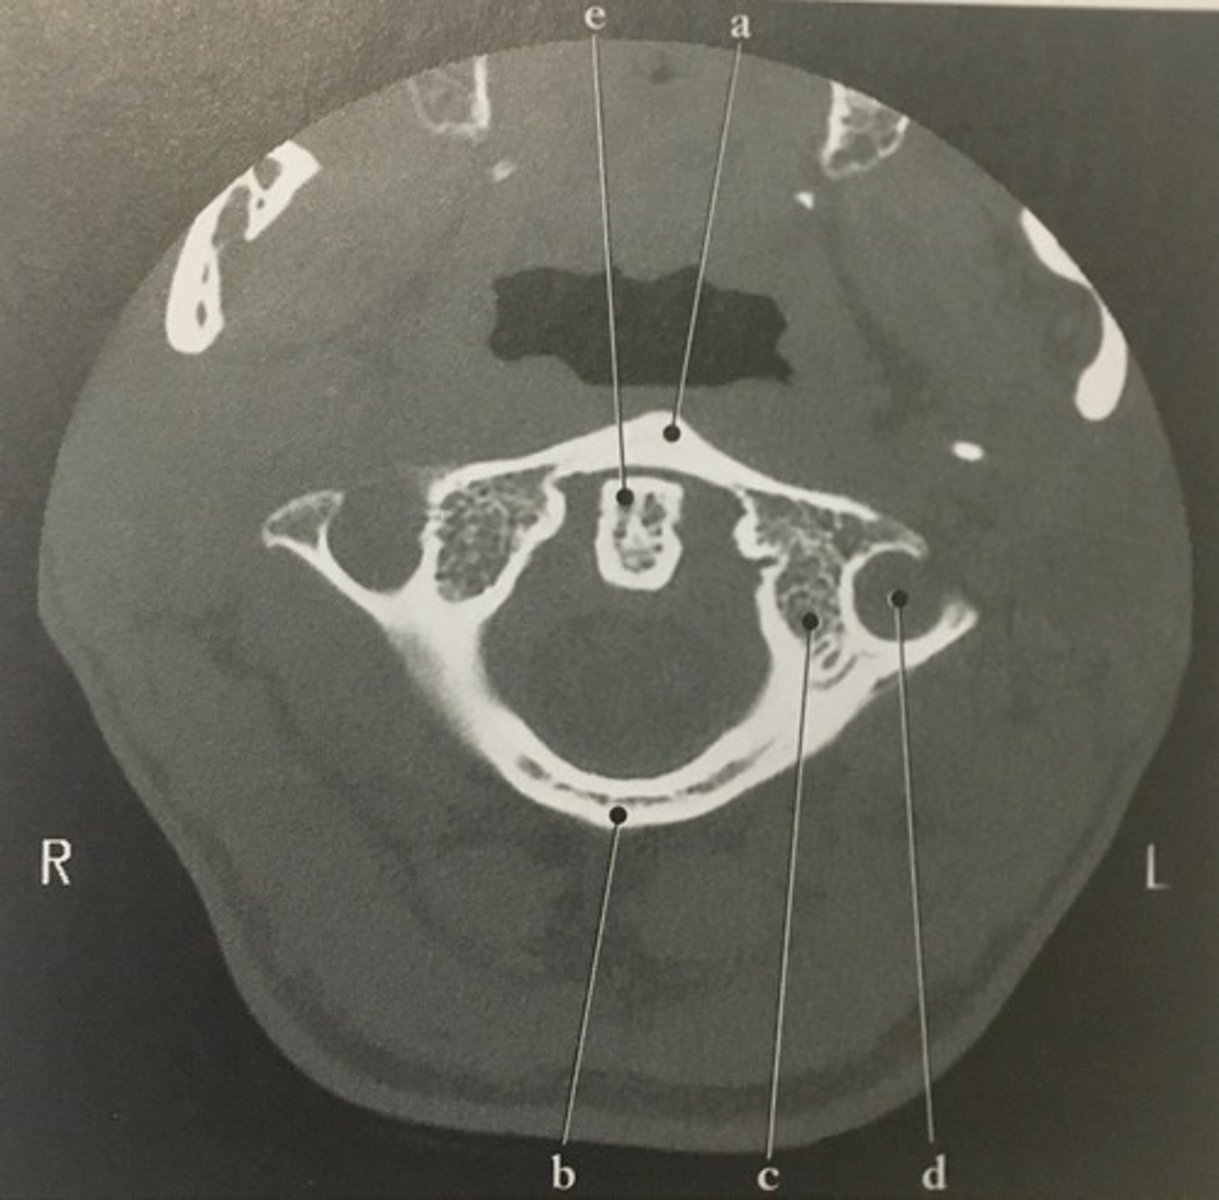

Identify structure A on this axial CT slice of the C1.

99

Posterior arch

<p>Identify structure B on this axial CT slice of the C1.</p>

New cards

Identify structure C on this axial CT slice of the C1.